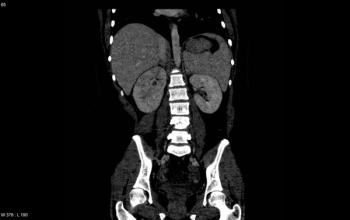

Can you diagnose this mostly asymptomatic patient but with weight loss and abdominal discomfort?

Can you diagnose this patient with unexplained weight loss?